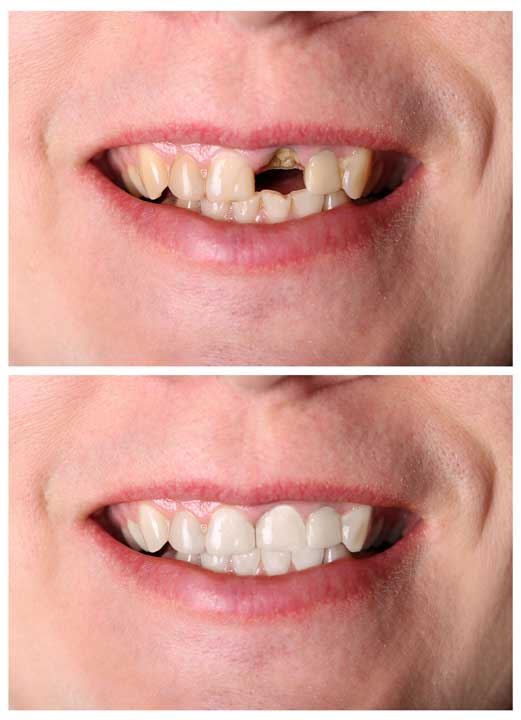

IMPLANTES

¿Qué son los implantes?

Los implantes

dentales osteointegrados son unos dispositivos de titanio, con diferentes tratamientos y recubrimientos de superficie. Su función es la de sustituir las raíces de los dientes naturales, sirviendo de soporte para la conexión, a través de los componentes protésicos, con la restauración definitiva, proporcionando confort, ajuste y estética.

¿Cuándo se colocan?

A cualquier edad

finalizando el crecimiento, siempre y cuando la calidad y cantidad del hueso receptor sea la adecuada. En el caso de que la cantidad de hueso sea insuficiente, se pondrán aplicar técnicas de aporte óseo mediante injertos.

¿A quién se le colocan?

Los implantes están

indicados en la mayoría de las personas

que llevan prótesis completas, o bien precisan la colocación de un puente o pieza dentaria aislada, ya que este caso no es necesario modificar los dientes adyacentes que pudieran estar sanos. Las contraindicaciones absolutas por otras enfermedades son escasas.